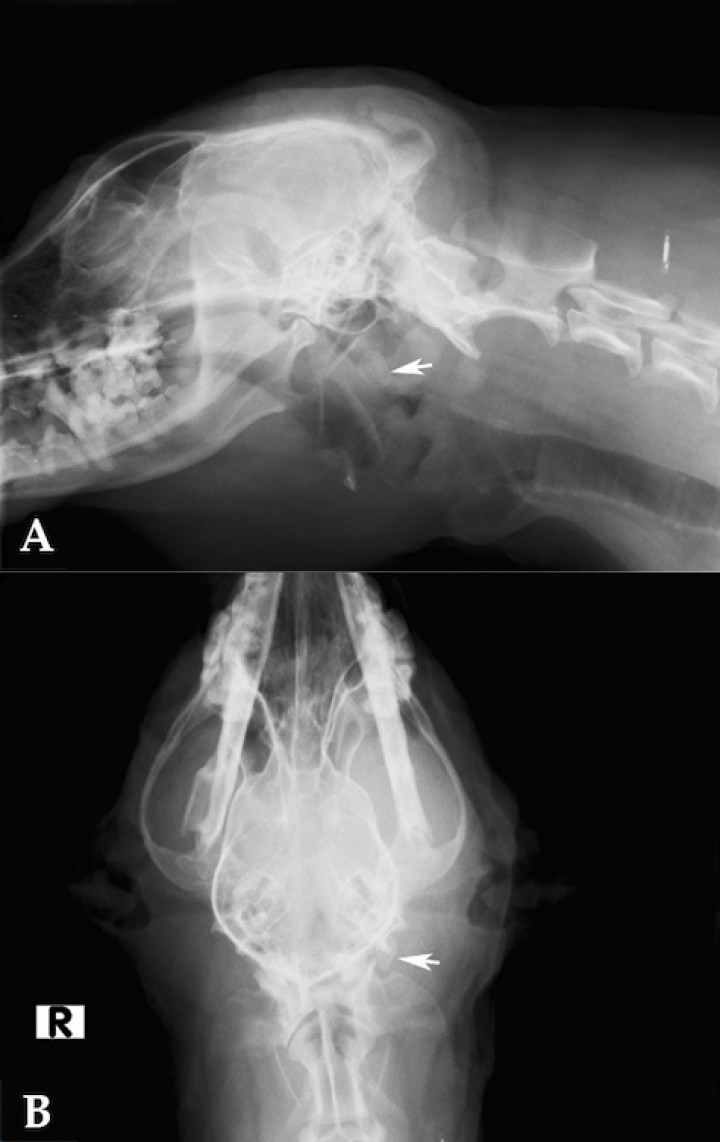

Se realizó un estudio radiológico del área cervical que puso de manifiesto la presencia de una estructura radiópaca, de 1,18 mm, en la región topográfica de glándula salival submandibular izquierda, siendo compatible con un sialolito (Fig. 2). Con los resultados obtenidos se diagnosticó un mucocele salival cervical asociado a la presencia de un sialolito.

<p>Radiografia lateral (A) y ventrodorsal (B) de cabeza y cuello. Se observa la presencia de un sialolito en región de glándula salival submandibular izquierda (flecha).</p>

Radiografia lateral (A) y ventrodorsal (B) de cabeza y cuello. Se observa la presencia de un sialolito en región de glándula salival submandibular izquierda (flecha).